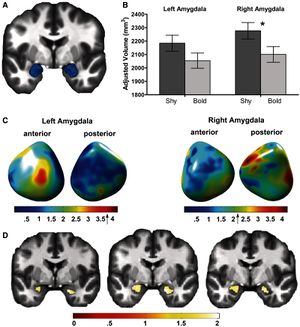

- 4.1 Structural and Functional Bases of Inhibited Temperament

- 4.2 Femoral and Tibial Insert Downsizing Increases the Laxity Envelope in TKA